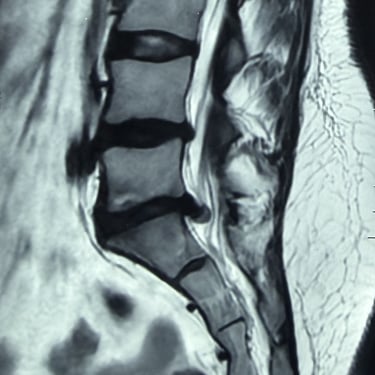

Manejo quirúrgico de la hernia lumbar con inestabilidad: enfoque moderno con FTP y TLIF

La hernia lumbar con inestabilidad vertebral es una patología frecuente que causa dolor lumbar persistente, ciática y limitación funcional, afectando la calidad de vida del paciente. Cuando el tratamiento conservador no logra resultados adecuados, la cirugía se convierte en la mejor opción terapéutica. La fijación transpedicular con tornillos (FTP) junto con la técnica TLIF (Transforaminal Lumbar Interbody Fusion) permite estabilizar la columna, descomprimir las estructuras nerviosas y lograr una adecuada fusión ósea. Este abordaje, especialmente mediante técnicas mínimamente invasivas (MISS), ofrece múltiples beneficios, como menor daño muscular, menor dolor postoperatorio y recuperación más rápida, facilitando el retorno temprano a las actividades cotidianas con mejores resultados clínicos.